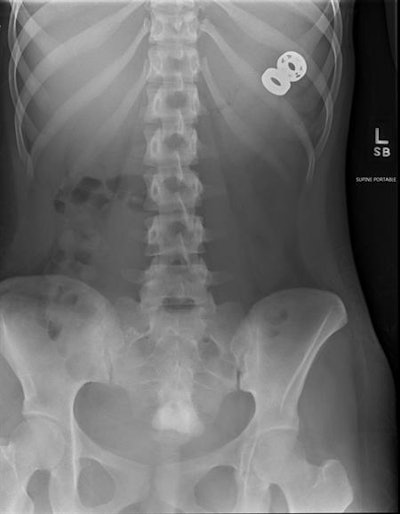

X-rays helped surgeons confirm the presence of an ingested fidget spinner toy in a patient and remove the metal parts via endoscopy, but they could not visualize plastic portions of it, according to a report published online February 22 in JAMA Otolaryngology -- Head and Neck Surgery.

A woman in her late teens with a "complex mental health history including depression and eating disorder" swallowed parts of a fidget spinner broken into three pieces, Otjen and colleagues wrote. X-ray and endoscopic evaluation confirmed the presence of parts of the object in the esophagus; they were taken out via rigid endoscopy.

Removing the toy proved challenging due to the fact that parts of it were impinging the esophagus and needed to be rotated. Follow-up x-ray three days later showed retropharyngeal gas, which prompted an additional week of intravenous feeding for the patient. Other parts of the toy passed normally some days later.

In cases of foreign body ingestion, it's important to consider that there may be parts x-ray can't identify, the researchers concluded.